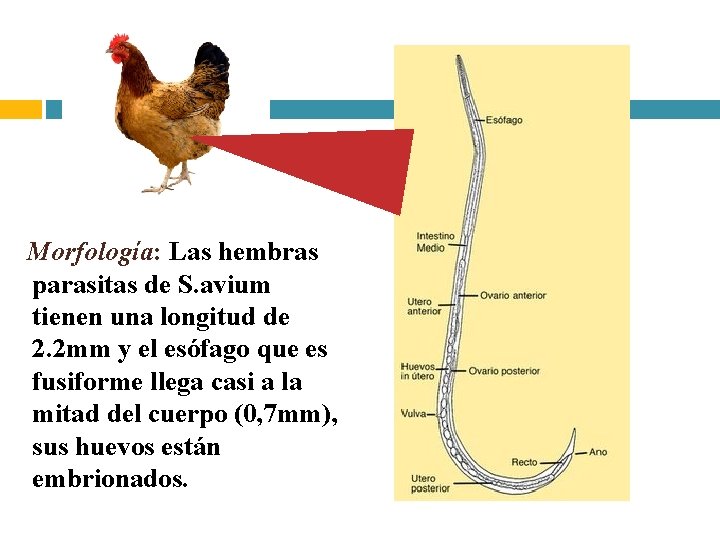

Morfología: Las hembras parasitas de S. avium tienen una longitud de 2. 2 mm y el esófago que es fusiforme llega casi a la mitad del cuerpo (0, 7 mm), sus huevos están embrionados.